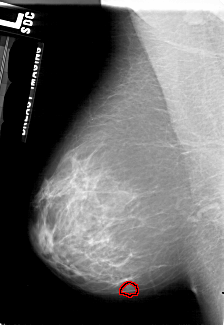

A_1758_1.LEFT_MLO

LEFT_MLO LINES 4861 PIXELS_PER_LINE 3346 BITS_PER_PIXEL 12 RESOLUTION 43.5 OVERLAY

FILE: A_1758_1.LEFT_MLO.OVERLAY

TOTAL_ABNORMALITIES 1

ABNORMALITY 1

LESION_TYPE MASS SHAPE LOBULATED MARGINS OBSCURED

ASSESSMENT 3

SUBTLETY 4

PATHOLOGY BENIGN

TOTAL_OUTLINES 1

BOUNDARY